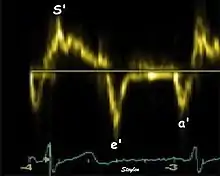

Systolic function

Peak systolic annular velocity (S') of the left ventricle is as close to a contractility measure as you can get by imaging[4] (bearing in mind that any imaging method only measures the result of fibre shortening, without measuring myocyte tension). S' has become a reliable measure of global function[5][6][7][8] It shares the advantage of annular displacement, that it is reduced also in hypertrophic hearts with small ventricles and normal ejection fraction (HFNEF), which is often seen in Hypertensive heart disease, Hypertrophic cardiomyopathy and Aortic stenosis.[9]

Diastolic function

As the ventricle relaxes, the annulus moves towards the base of the heart, signifying the volume expansion of the ventricle. The peak mitral annular velocity during early filling, e' is a measure of left ventricular diastolic function, and has been shown to be relatively independent of left ventricular filling pressure.[12][13][14] If there is impaired relaxation (Diastolic dysfunction), the e' velocity decreases. After the early relaxation, the ventricular myocardium is passive, the late velocity peak a' is a function of atrial contraction. The ratio between e' and a' is also a measure of diastolic function, in addition to the absolute values.

During the two filling phases, there is early (E) and late (A) blood flow from the atrium to the ventricle, corresponding to the annular velocity phases. The flow, is driven by the pressure difference between atrium and ventricle, this pressure difference is both a function of the pressure drop during early relaxation and the initial atrial pressure. In light diastolic dysfunction, the peak early mitral flow velocity E is reduced in proportion to the e', but if relaxation is so reduced that it causes increase in atrial pressure, E will increase again, while e', being less load dependent, remains low. Thus, the ratio E/e' is related to the atrial pressure, and can show increased filling pressure[15][16] although with several reservations.[17][18] In the right ventricle this is not an important principle, as the right atrial pressure is the same as central venous pressure which can easily be assessed from venous congestion.[19][20]